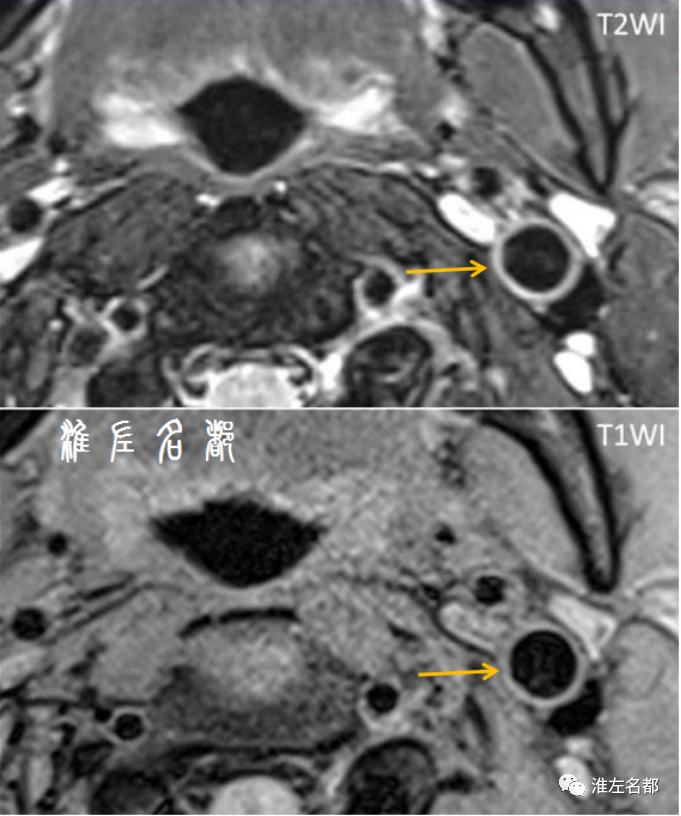

其实,得益于优良的软组织分辨力,磁共振在早期即已应用于大动脉的管壁病变成像研究了,如主动脉和髂动脉,这是因为大动脉血流速度快,且对空间分辨率要求不高,常规黑血序列即可满足。然而,由于颈动脉管径相对小,且易受搏动和呼吸影响,所以直到1.5T高场强磁共振机的问世,以及专用的表面线圈应用,才实现了此部位的高清晰管壁成像。此外,由于颈动脉内膜剥脱术的开展,使其可与病理结果做对照,发现二者高度吻合,这极大加深了对颈动脉斑块的病理生理机制认识。

颅内动脉受血管搏动和呼吸运动影响极小,位置相对固定,这一点来说,是行管壁高分辨MRI的优势。但另一方面,也存在诸多不利因素,如管径细小,管壁菲薄,且沿脑组织表面移行,这就要求高空间分辨率,高图像信噪比,以及高组织对比度,以实现在很小空间内显示管壁病变的不同病理组织差异;而且颅内动脉行程迂曲,如何消除血流相关伪影也是很大的挑战。

虽然十几年前就有学者首次报道了成功采用1.5T磁共振对管径相对粗大的颅内椎动脉进行管壁成像,后续少数的早期文献也报道了运用1.5T磁共振进行颅内其他血管管壁成像的研究。但总体而言,文献报道和现实实践中绝大部分情况下是采用场强更高的3.0T磁共振进行颅内血管的管壁高分辨成像,其优点包括:缩短扫描时间、提高空间分辨率、增加图像信噪比以及可实现高质量三维成像。

尽管困难重重,但临床还是迫切需要一种适用于颅内血管病变的管壁评估技术,以解决长期的诊治实践困境。十几年前即有多名学者应用高场强磁共振(主要是3.0T MRI)成功实现了临床应用水平的颅内动脉管壁成像,随后此技术引起广泛重视,相关研究的文献报道越来越多,在成像技术、图像处理、结果判读和诊治应用方面获得了长足发展。并且,国内外均发表了颅内管壁MRI技术的相关专家共识,以指导该技术的临床实施和应用。